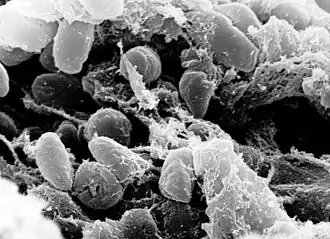

| A scanning electron micrograph depicting a mass of Yersinia pestis bacteria in the foregut of an infected flea | |